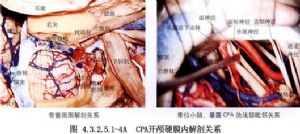

3.瓣形或放射狀切開硬腦膜,用絲線懸吊牽開。用腦壓板將小腦半球向內側牽開,撕開小腦延髓池及橋池蛛網膜,排出腦脊液,使顱內壓減低。沿顱後窩外側向小腦腦橋探查。接近內耳孔時,可發現腫瘤。聽神經瘤多呈灰紫色或灰褐色,腫瘤有退變,囊性變者呈黃褐色。有時腫瘤表面與蛛網膜粘連或由腦脊液積蓄形成囊腫(圖4.3.2.5.1-5B)。

4.切除腫瘤 一般先電凝腫瘤包膜,縱行切開,用吸引器、活檢鉗或刮匙行囊內腫瘤切除(圖4.3.2.5.1-6)。如切除腫瘤時出血較多,可先從腫瘤周邊遊離,進入腫瘤下極。內側與上極的小供血動脈一一電凝後切斷,再繼續從囊內切除腫瘤。囊內切除瘤組織愈多,腫瘤包膜塌陷愈好,有利於腫瘤切除。

5.將腫瘤下極自第9、10、11顱神經分開,再遊離腫瘤內側面與上極。遊離上極時必須先電凝由小腦上動脈至腫瘤的分支,並予以切斷。而後將腫瘤自三叉神經分離,如腫瘤已向上突入小腦幕裂孔,小心將腫瘤向下牽拉,以便分塊切除。將腫瘤包膜牽向外側,看清位於腫瘤前下方的面神經,使面神經由腫瘤包膜遊離至靠近內耳孔處(圖4.3.2.5.1-7)。再將腫瘤由內耳孔處切斷,摘除腫瘤(圖4.3.2.5.1-8)。

殘留於內耳孔內的腫瘤組織,可用高速微型鑽磨開內耳道後壁,顯露內耳道內的腫瘤部分,將其切除,勿損傷面神經(圖4.3.2.5.1-9)。當腫瘤已從囊內基本切除後,由於其內側面與腦幹粘連緊密或嵌入腦幹內時,有時極難分離,如強行剝離,將加重腦幹損傷。手術可做到大部切除,而採用雙極電凝將腫瘤殘餘部分電凝,破壞瘤組織。囊性聽神經瘤與腦幹、顱神經的粘連較緊,界面不清,特別需要術中仔細辨認。